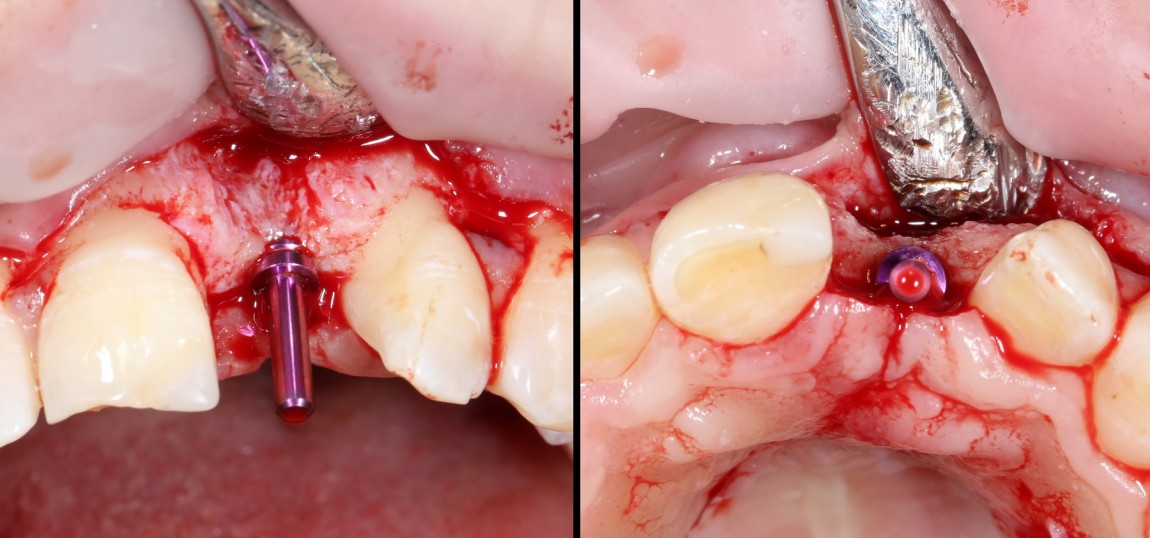

Делаем анестезию, разрез, скелетируем костную ткань:

На фотографиях хорошо видны оставшиеся после удаления объемы костной ткани. Давайте рассмотрим плюсы и минусы текущей клинической ситуации, применительно к нашему плану:

Фактически, альвеолярный гребень атрофировался по толщине примерно наполовину — это минус.

Зато с высотой все в порядке — это плюс

Немедленная нагрузка на имплантат невозможна — это минус. Почему? (см. Факторы…)

Достаточный объем кератинизированной десны, который даст нам возможность герметично запечатать послеоперационную рану — это, несомненно, тоже плюс. (вспомним факторы успеха остеопластической операции, часть III)

Ну и, оставшиеся объемы костной ткани позволят нам установить и правильно позиционировать имплантат — это главный плюс. А значит, мы обойдемся одной операцией вместо двух.

Итак, позиционируем имплантат. Для начала, с помощью пина:

Напомню правило позиционирования в области фронтальной группы зубов:

Ось импланта выходит на небную поверхность будущей коронки. Или, в крайнем случае, на режущий край.

Лунка готова, устанавливаем имплантат:

Это Nobel Replace CC 3.5×13 mm. Оптимальный размер импланта для работы в этом клиническом случае.